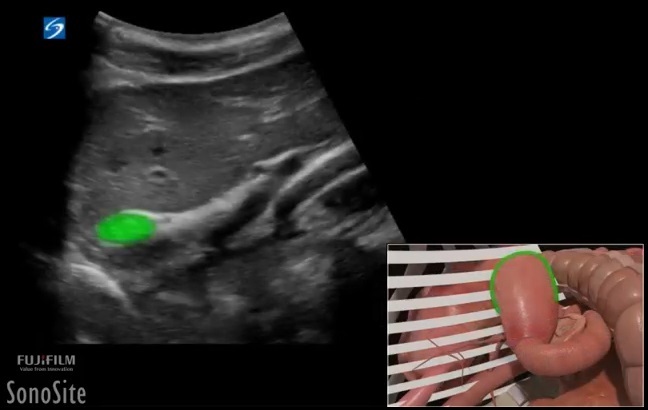

Gastric Content Gastric Antrum